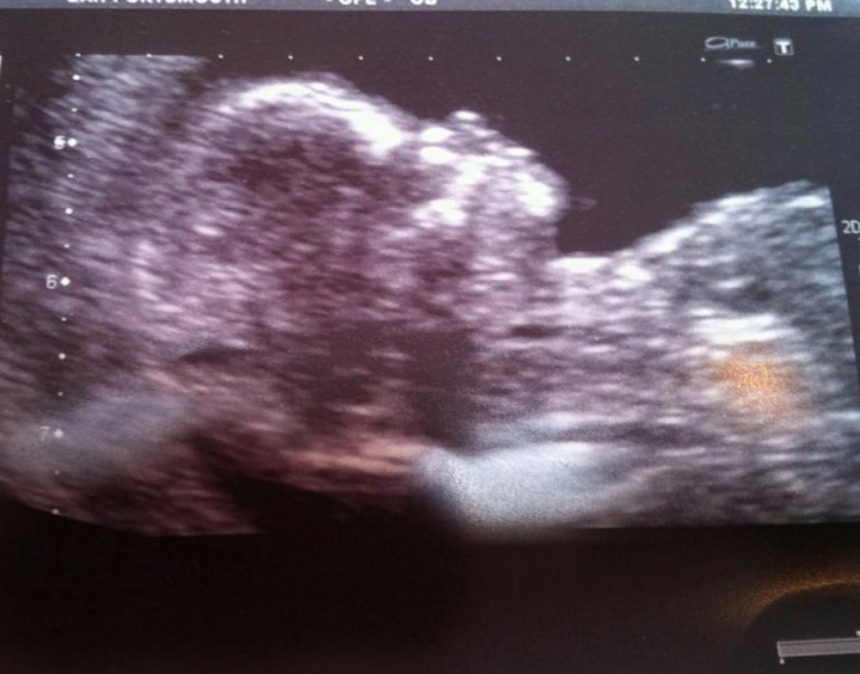

Нејзиното момче кое било постаро ипоискусно се обидувало да ѝ помогне но по неколку неуспешни обиди за се*с, парот решил да остане на други опции. Затоа кога на Никол почнало да ѝ се лоши и една пријателка ѝ кажала дека можеби е бремена на девојката ѝ било смешно, но одлучила да направи тест за бременост. Кога тој испаднал позитивен шокот бил уште поголем.

„За време на бременоста, ми беше многу тешко да им ја објаснам мојата состојба на лекарите секој пат. Го донесов мојот дечко, и тој им се заколна дека немаме секс. И кога на прегледот ја замолив медицинската сестра да биде повеќе внимателен, бидејќи во овој поглед, јас сè уште бев девица, таа само се насмеа: „Па, да, секако.“ Само тогаш лекарот ми објасни дека иако нема пенетрација, спермата сепак може лесно да влезе внатре “, вели Никол Мур.

За време на бременоста Никол успеала да најде лекар кој ќе ѝ помогне да ја третира нејзината состојба и во 5-тиот месец од бременоста ја изгубила невиноста. Сега нејзината ќерка има 7 години и таа повеќе не е со нејзиното момче, но вели дека е среќна што сама го расте своето дете.